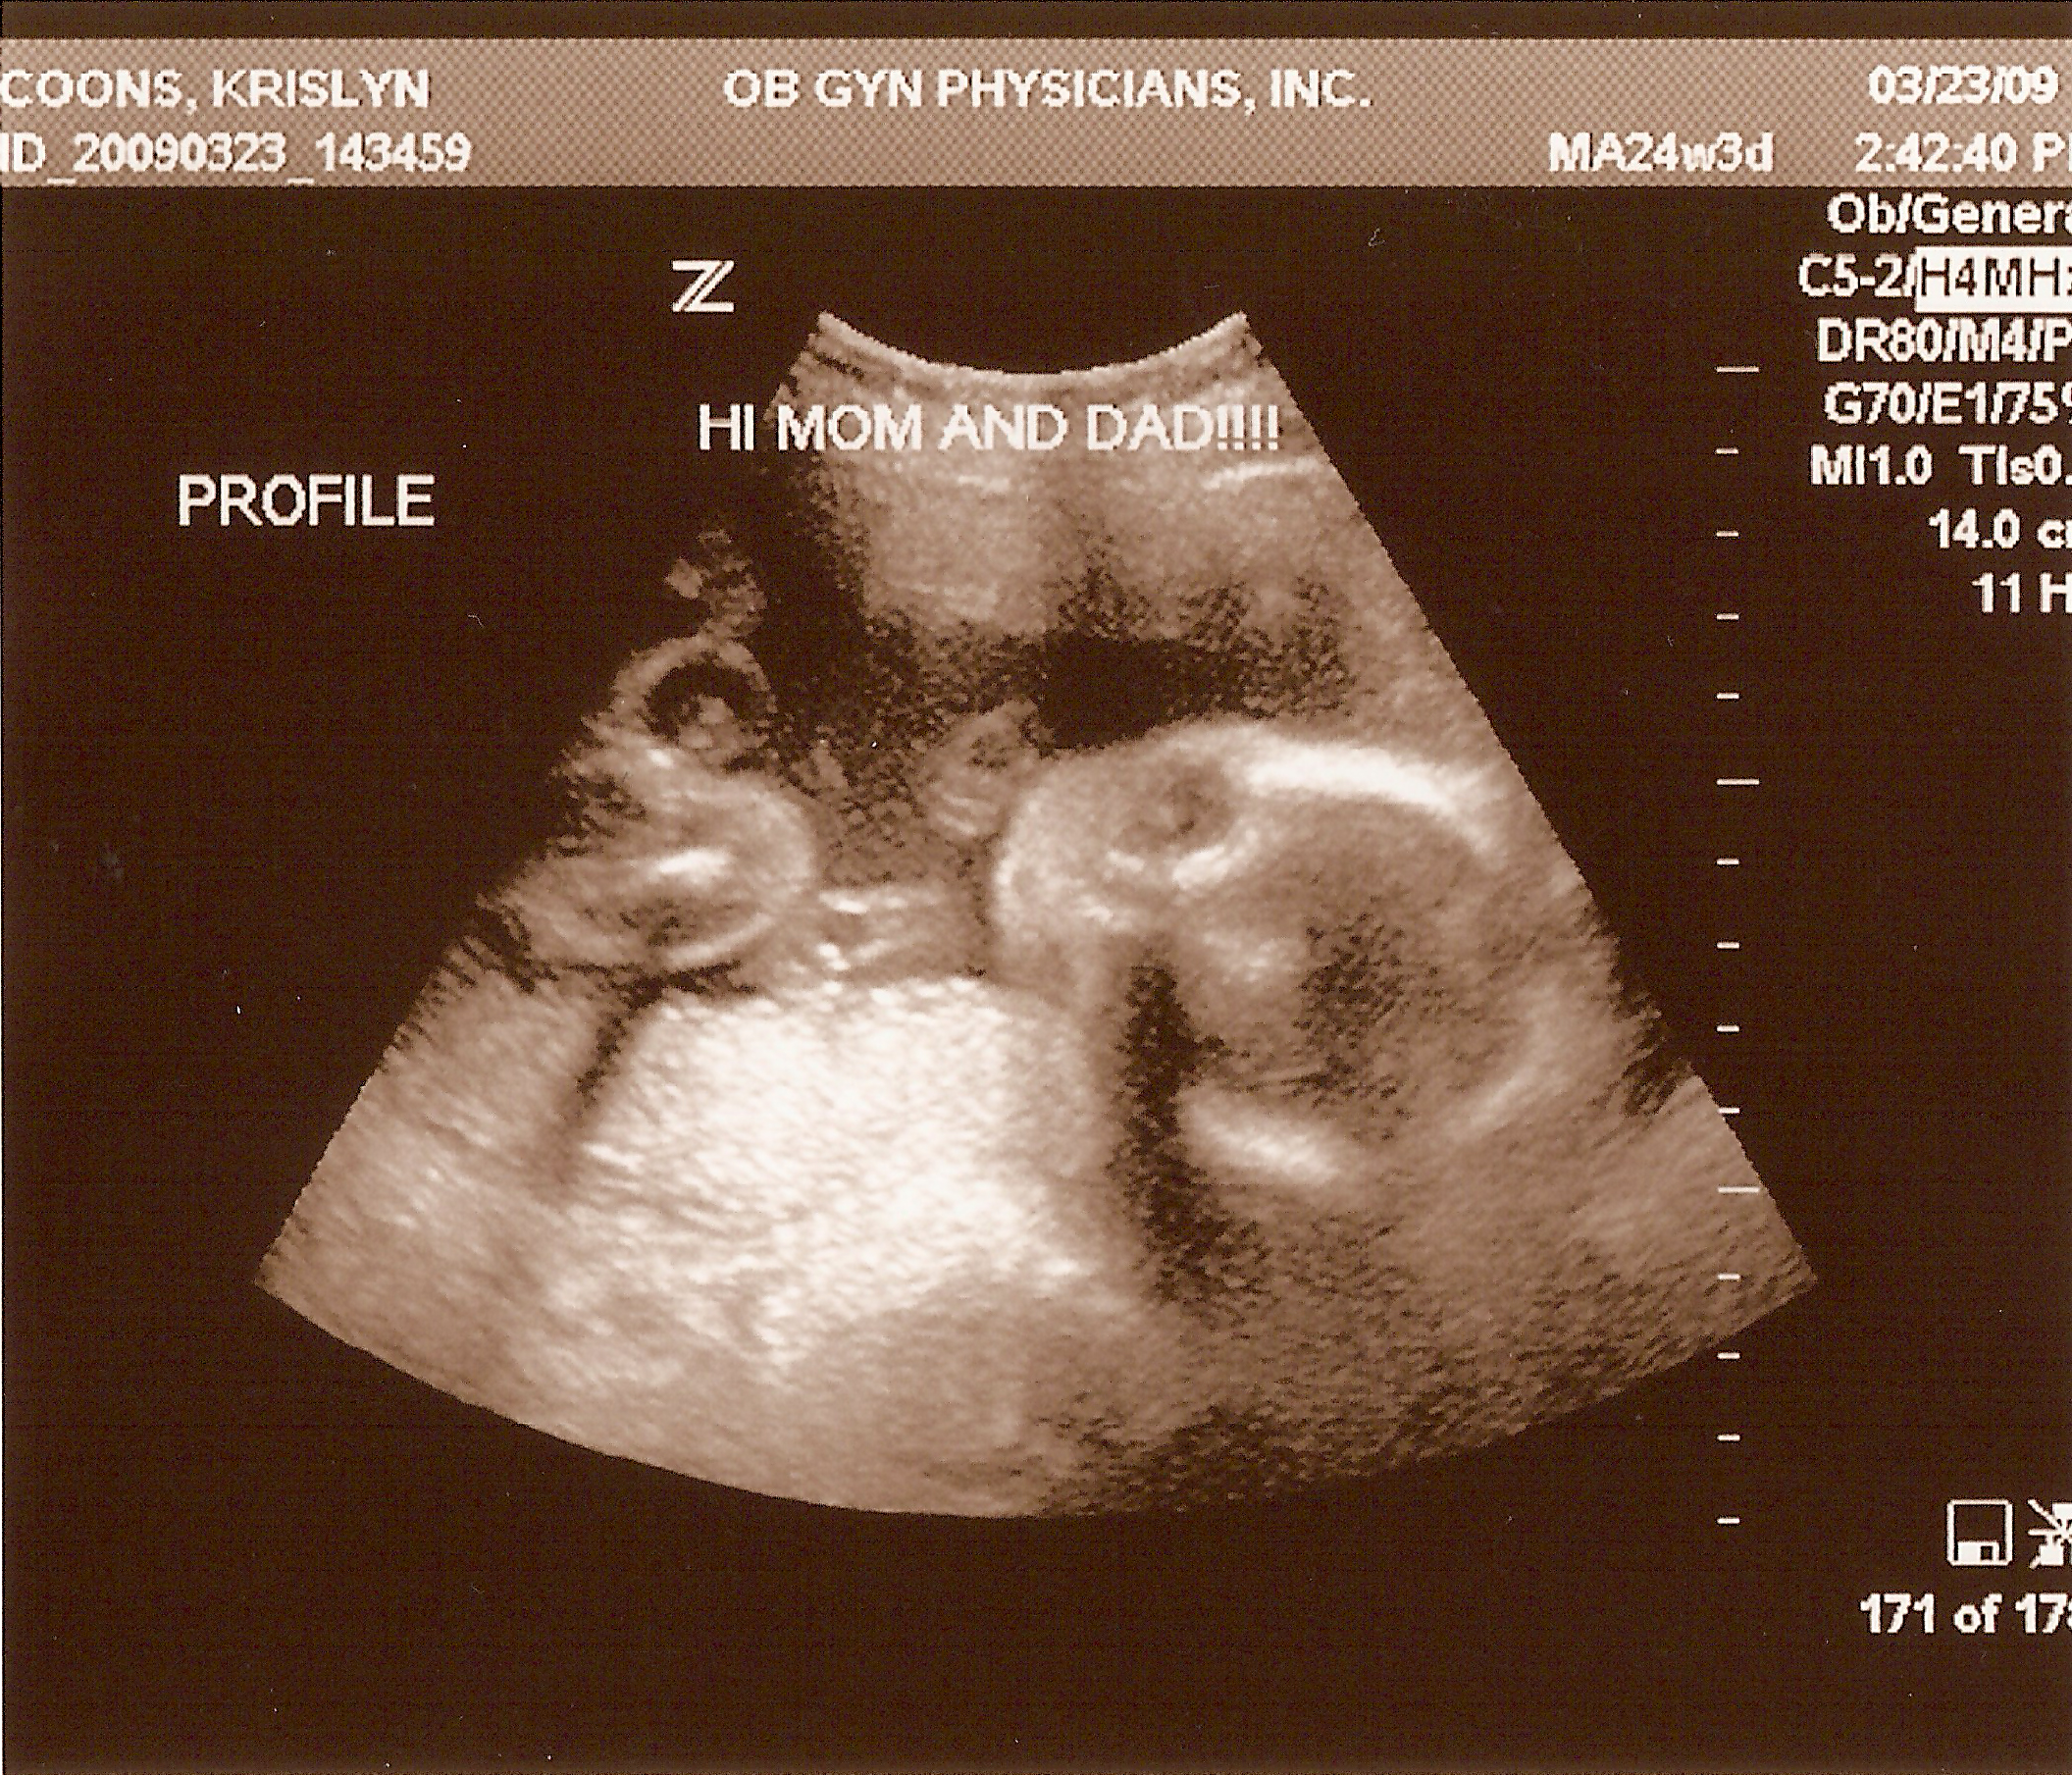

24 weeks

3.23.2009

Second ultrasound! Baby is doing well and all measurements checked out--weighing in around 1.7 pounds. No abnormalities on the PentaScan, so no need for an amnio. And Krislyn is really starting to show now!